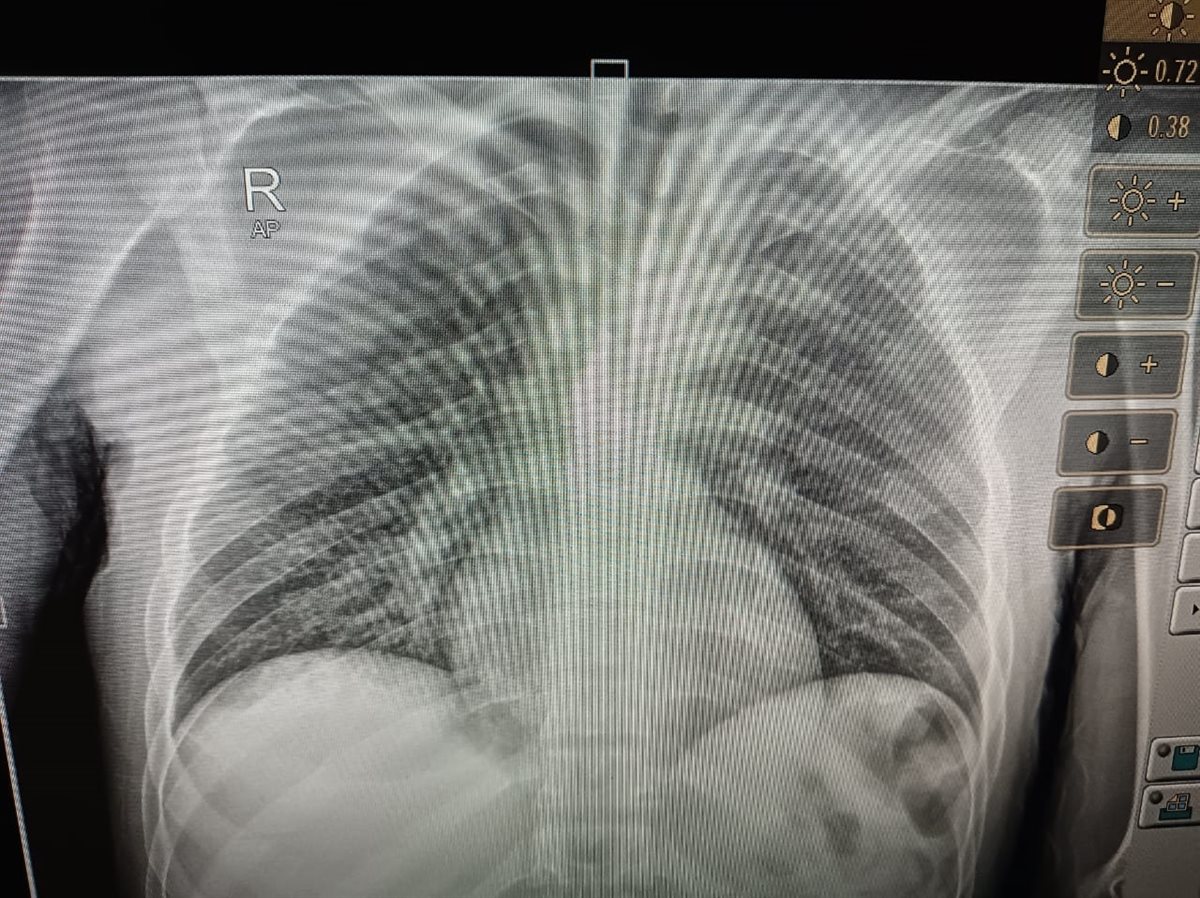

المريض بورم في المخ

استغاث شقيق مريض ورم بالمخ، من رفض مستشفى الحسين استقبال الأخير بالعناية المركزة، حيث يعاني من مضاعفات صحية شديدة من فقدان النطق، بعد 4 أشهر من إجراء عملية لإزالة الورم في المستشفى.

وأوضح مصطفى شقيق المريض في تصريحات خاصة لـ القاهرة 24: شقيقي عانى من مضاعفات صحية شديدة بعد 4 أشهر من إجراء عملية إزالة الورم بالمخ في مستشفى الحسين، وعندما ذهبنا لهم خلال هذه الأيام لعلاجه أو لتشخيصه أخبرونا أنه يحتاج لعناية مركزة وأعداد المرضى مكتملة، ولا يوجد أي طاقة استيعابية في العناية المركزة لاستقبال أي مريض، والحالة دي بتسوء مني وليس لدي أي مقدرة لدخوله عناية مركزة بمستشفى خاص.